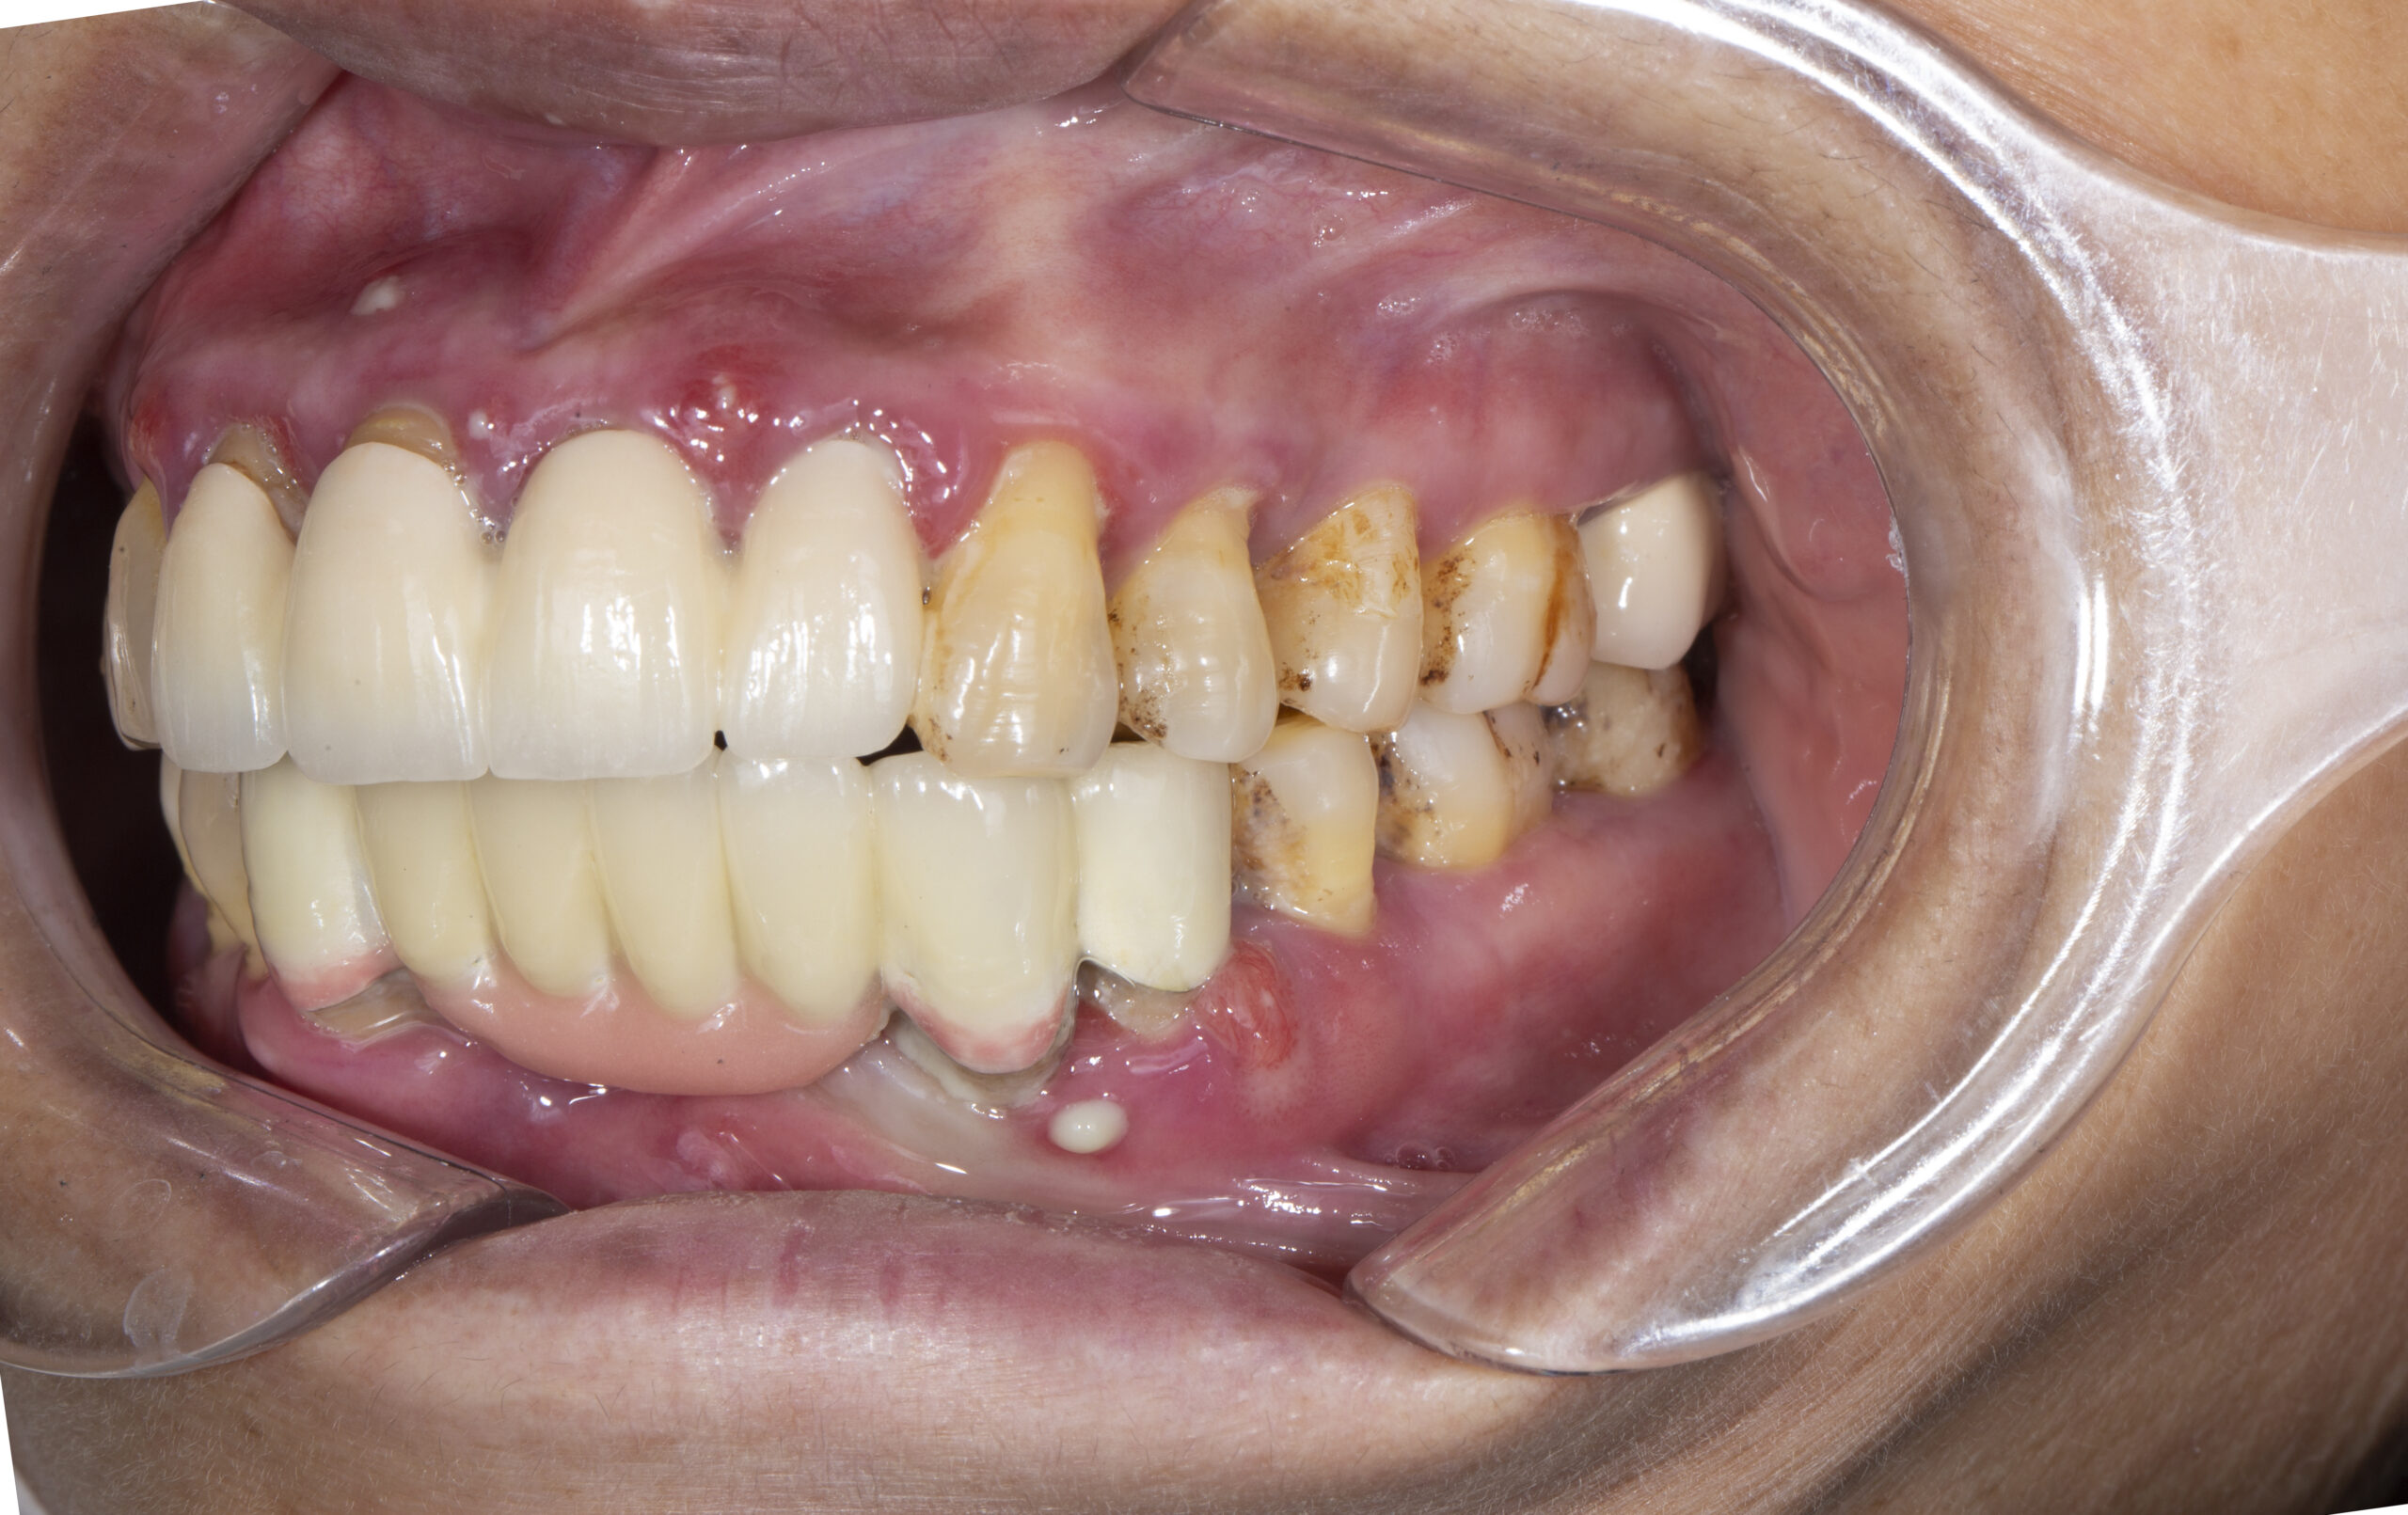

Cô khách hàng 60 tuổi quyết tâm thay đổi từ cầu răng sứ sang trồng răng Implant

Ghi chú quan trọng (đọc kỹ)

-

Bảng trên chưa bao gồm: chi phí tăng thể tích xương hàm bị thiếu (ghép xương) và nâng nền xoang bị sà xuống nếu cần — các chi phí này phát sinh theo tình trạng xương thực tế. (Tham khảo: tăng thể tích xương 3–10 triệu; nâng nền xoang 5–10 triệu.)